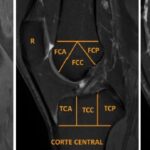

Se evaluaron de forma independiente los estudios de resonancias magnéticas para detectar la presencia de edema óseo (0 = no, 1 = sí) en la tibia, fémur y la rótula, realizando las adquisiciones de resonancia magnética con reconstrucciones en planos axial, sagital y coronal ponderadas en las secuencias T1, T2, STIR. Para el estudio de la articulación se dividió en 20 regiones anatómicas (Figura 1), utilizando un método de segmentación para la evaluación del edema óseo. La evaluación se realizó por médicos especializados en imágenes musculoesqueléticas, quienes cuentan un alto nivel de formación y entrenamiento en el diagnóstico de patologías articulares de la rodilla, estableciéndose los siguientes protocolos estudio:

IV. Análisis de imágenes. Se revisaron de forma independiente los estudios de resonancias magnéticas para detectar la presencia de edema óseo. Para el estudio de la articulación se dividió en 20 regiones anatómicas como método de segmentación. La evaluación fue realizada por médicos especializados en imágenes musculoesqueléticas, quienes cuentan un alto nivel de formación y entrenamiento en el diagnóstico de patologías articulares de la rodilla.